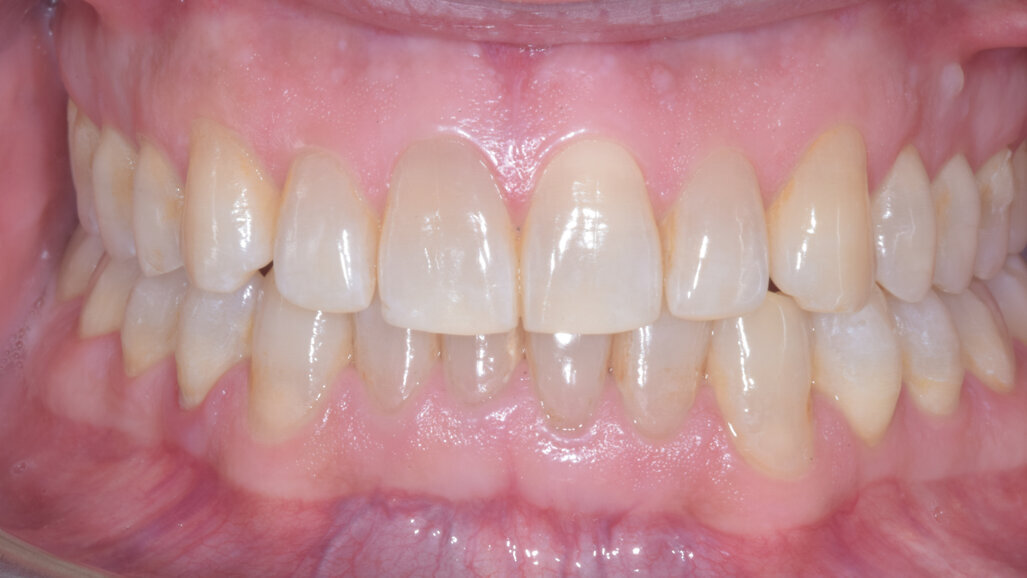

À la fin du traitement, on pouvait observer une relation de classe I des canines et des molaires, une légère augmentation de l’inclinaison des incisives supérieures (Ui-FH = 112°), une correction complète de l’inclinaison des incisives inférieures (IMPA = 97,09°) grâce à la vestibulo-version, et une légère amélioration de l’hypodivergence (SN-GoGn = 27°) résultant de l’extrusion relative des dents postérieures, et de l’utilisation d’élastiques de classe II — petite variation (1°) très intéressante compte tenu de l’âge du patient (Figs. 25–35). La ligne du sourire était harmonieuse et correspondait à une relation idéale entre les incisives supérieures et la lèvre inférieure. Le sourire avait été élargi grâce au contrôle du torque des segments latéraux et postérieurs.

La ligne du sourire était harmonieuse et correspondait à une relation idéale entre les incisives supérieures et la lèvre inférieure. Le sourire avait été élargi grâce au contrôle du torque des segments latéraux et postérieurs. La superposition des tracés céphalométriques montrait des changements intéressants induits par le traitement orthodontique (Figs. 36 et 37) :

• L’inclinaison des incisives supérieures était réduite d’environ 2° (de 110° à 112°) par rapport au plan maxillaire, et l’inclinaison des incisives inférieures était réduite d’environ 6° (de 91° à 97°) par rapport au plan mandibulaire. La relation interincisive était satisfaisante et le soutien symphysaire suffisant.

• L’extrusion relative des molaires supérieures et inférieures, combinée avec l’utilisation de rampes d’occlusion, avait mené à une légère rotation de la mandibule dans le sens horaire (SN-GoGn de 26° à 27°), ce qui avait d’autant plus amélioré le recouvrement incisif.

• La vestibulo-version des incisives supérieures et inférieures avait amélioré le profil et le soutien labial.

Lors du suivi à un an, alors que le patient portait un appareil de rétention (appareil de rétention Vivera avec rampes d’occlusion, Align Technology), le résultat était stable et l’intercuspation était nettement meilleure (Figs. 38–42).